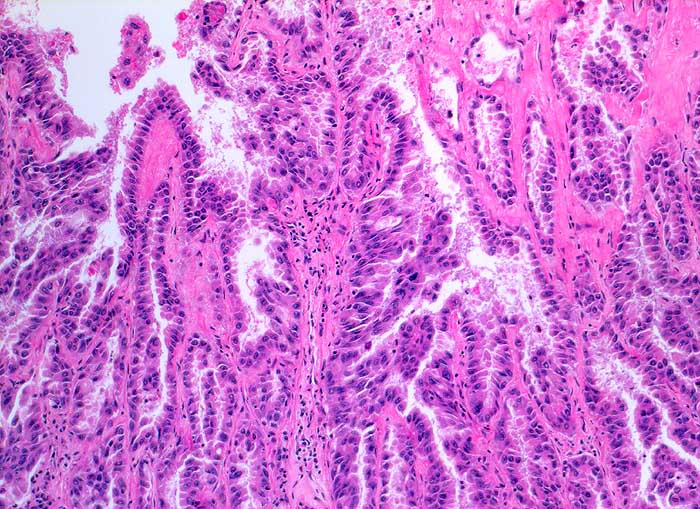

Adenokarzinome der Lunge lassen sich von Adenokarzinomen anderer Primärlokalisation zytologisch nicht unterscheiden. Die Zellen sind meist grösser als Mesothelien und die Kernatypien deutlich ausgeprägt. Falls die Lokalisation des Primärtumors nicht bekannt ist, kann eine immunzytochemische Untersuchung mit TTF1, CK7 und CK20 weiterhelfen. Über 70% der Adenokarzinome der Lunge sind TTF1 positiv. Bei TTF1 Positivität der Tumorzellen sollte ein Schilddrüsenkarzinom ausgeschlossen werden. Unten gezeigt werden zwei verschiedene Fälle.